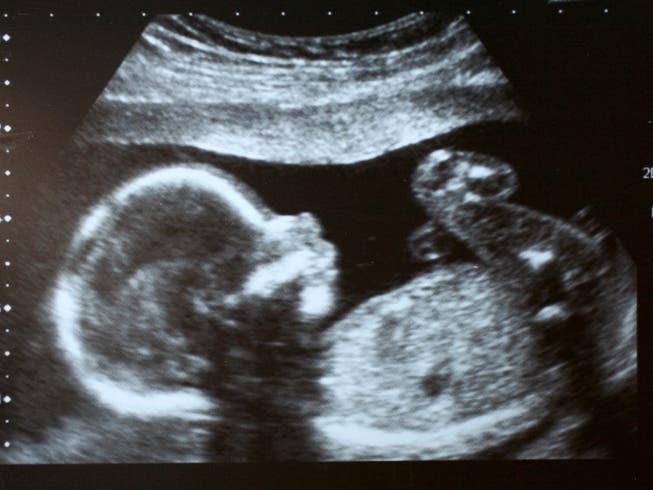

The law, which had been barred from taking effect, bans most abortions once a "detectable human heartbeat" is present. Cardiac activity can be detected by ultrasound in cells within an embryo that will eventually become the heart as early as six weeks into a pregnancy before many pregnancies are detected.

The new guidance will be in place when Georgia residents file for tax year 2022, according to state officials. It will apply to any taxpayer who was carrying an unborn child with a detectable heartbeat between July 20 and Dec. 31, 2022.

According to state officials, the taxpayer may claim a personal exemption of $3,000 for each unborn child. Medical records or other supporting documentation will be required to support the claim, officials said.